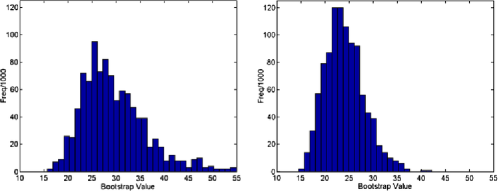

Figure 8 shows four typical examples of bootstrap distributions with and without changes detected. While differences due to the different underlying correlation structures are clearly visible, no difference is apparent between scans which contain a detected change and those which do not. Figure 9 shows the distribution of the 5% bootstrap critical values from 197 scans, once more indicating that the critical values show some deviation between scans due to different underlying correlation structures, hence different limit distributions, but do not differ between those with or without changes detected.